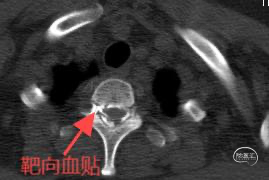

明确瘘口之后,接受了T10-11靶向血贴治疗。

患者术后24小时即可下床活动,头痛消失,之前伴随症状明显改善,康复出院。